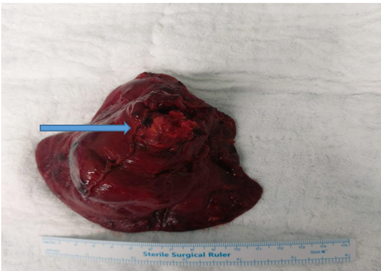

The thoracic team proceeded with rigid bronchoscopy, identifying and removing friable granulation tissue and fresh clots from the right lower lobe bronchus. Despite those measures, bleeding persisted, prompting immediate thoracotomy and right middle lobectomy. Intraoperatively, a mass was found at the upper part of the right lower lobe extending into the middle lobe, necessitating careful resection of the right lower lobe up to but preserving the right middle lobe and bronchus (Figure 3).

Figure 3: Resected specimen Right lower lobe with tumor infiltrating the Right lower lobe bronchus.